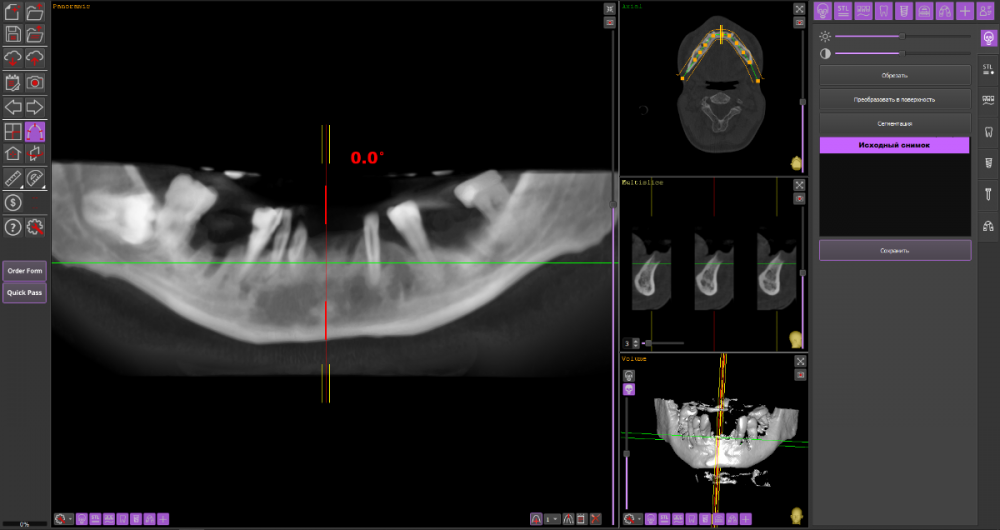

Сергей34 Опубликовано 5 ноября, 2022 Поделиться Опубликовано 5 ноября, 2022 Уважаемые доктора, надеюсь на ваше понимание - дело возможно для вас обыденное, пациенту очень сложно. Мне 34 года. Вот ссылка на архив с 3 д кт. https://drive.google.com/drive/folders/1sEpt1GplfkE7_Y9vTtyIFoQWssskl3XU?usp=sharing Кратко про истории болезни, недоразвитвая нижняя челюсть, неправильный прикус, пародонтит с самых юных лет. Итого в 34 года я продолжаю терять зубы - условно здоровые, альвиола убывает. Насколько мне обьяснили врачи в реале, на нижнюю челюсть можно поставить 6 имплантов без подсадки кости. На верху только с синусом (синус не потяну, слишком дорого обходится для меня). Без синуса только 4 импланта можно установить. Изначально я думал протезировать пока только низ, а верх оставить на потом. Но как мне обьяснили опять таки это будет риском для нижних конструкций, тем более учитывая активную убыль кости на верхней челюсти это лишь дело времени - не столь отдалённого, но там может оказаться так что и эти 4 импланта будет затруднительно поставить из за продолжающейся убыли. Врач мне сказал что при состоянии моих десён, ставить импланты сразу нельзя - нужно удалив все зубы подождать восстановления связок, ран 8 недель, после чего поставить импланты и дать им прижиться 3 месяца. А моя работа связанна с переговорами, если я не говорю я не работаю = теряю приток средств на эти манипуляции. Я чисто физически не могу себе позволить так долго находится вне рабочем состоянии. Итого у меня 2 вопроса на которые я конкретные ответы так и не смог получить от докторов; 1.Возможно ли изготовить и носить (будут ли держаться) простые съёмные протезы спустя 15 дней к примеру после удаления зубов ( в рабочее время 4-5 ч в день) не используя их для употребления пищи? Сильно ли это ношение отрицательно сказывается на восстановлении для дальнейшей имплантации? 2.С нижней челюстью на первый взгляд всё понятно, туда возможно на 6 имплантов установить метало-керамику из 12 зубов. А что с верхом? На 4 импланта ставить условно-сьёмный протез тем более что мне всего 34 года, как я понимаю эта конструкция не слишком надёжна всю нагрузку распределять всего на 4 импланта? Альтернативой может являться сьёмный протез на балке или без балки? Из акрила например или какой ещё материал возможен? Чтобы они с протезом нижней челюсти (к примеру метало-керамикой) друг друга не перетёрли ? 3.Главный вопрос учитывая склонность десён к пародонтиту, даже если убрать все зубы (пусть даже с правильной гигиеной), имеются шансы что болезнь будет вокруг имплантов продолжать свои злоключения - стоит ли эта игра всех этих трат? Или дешевле и проще будет поставить на низ 2 импланта и на верх 2 импланта и сделать на них протезы? И терять потом если что будет не так накладно по деньгам. Прошу помочь консультацией. Очень требуется по человечески помощь, я так сильно запутался что не знаю что делать просто и порой единственным решением кажется просто удалить остатки зубов и сделать простые сьёмные протезы. Всем кто зайдёт в тему, найдёт или не найдёт даже время высказать мнение - заранее благодарен. Ссылка на комментарий